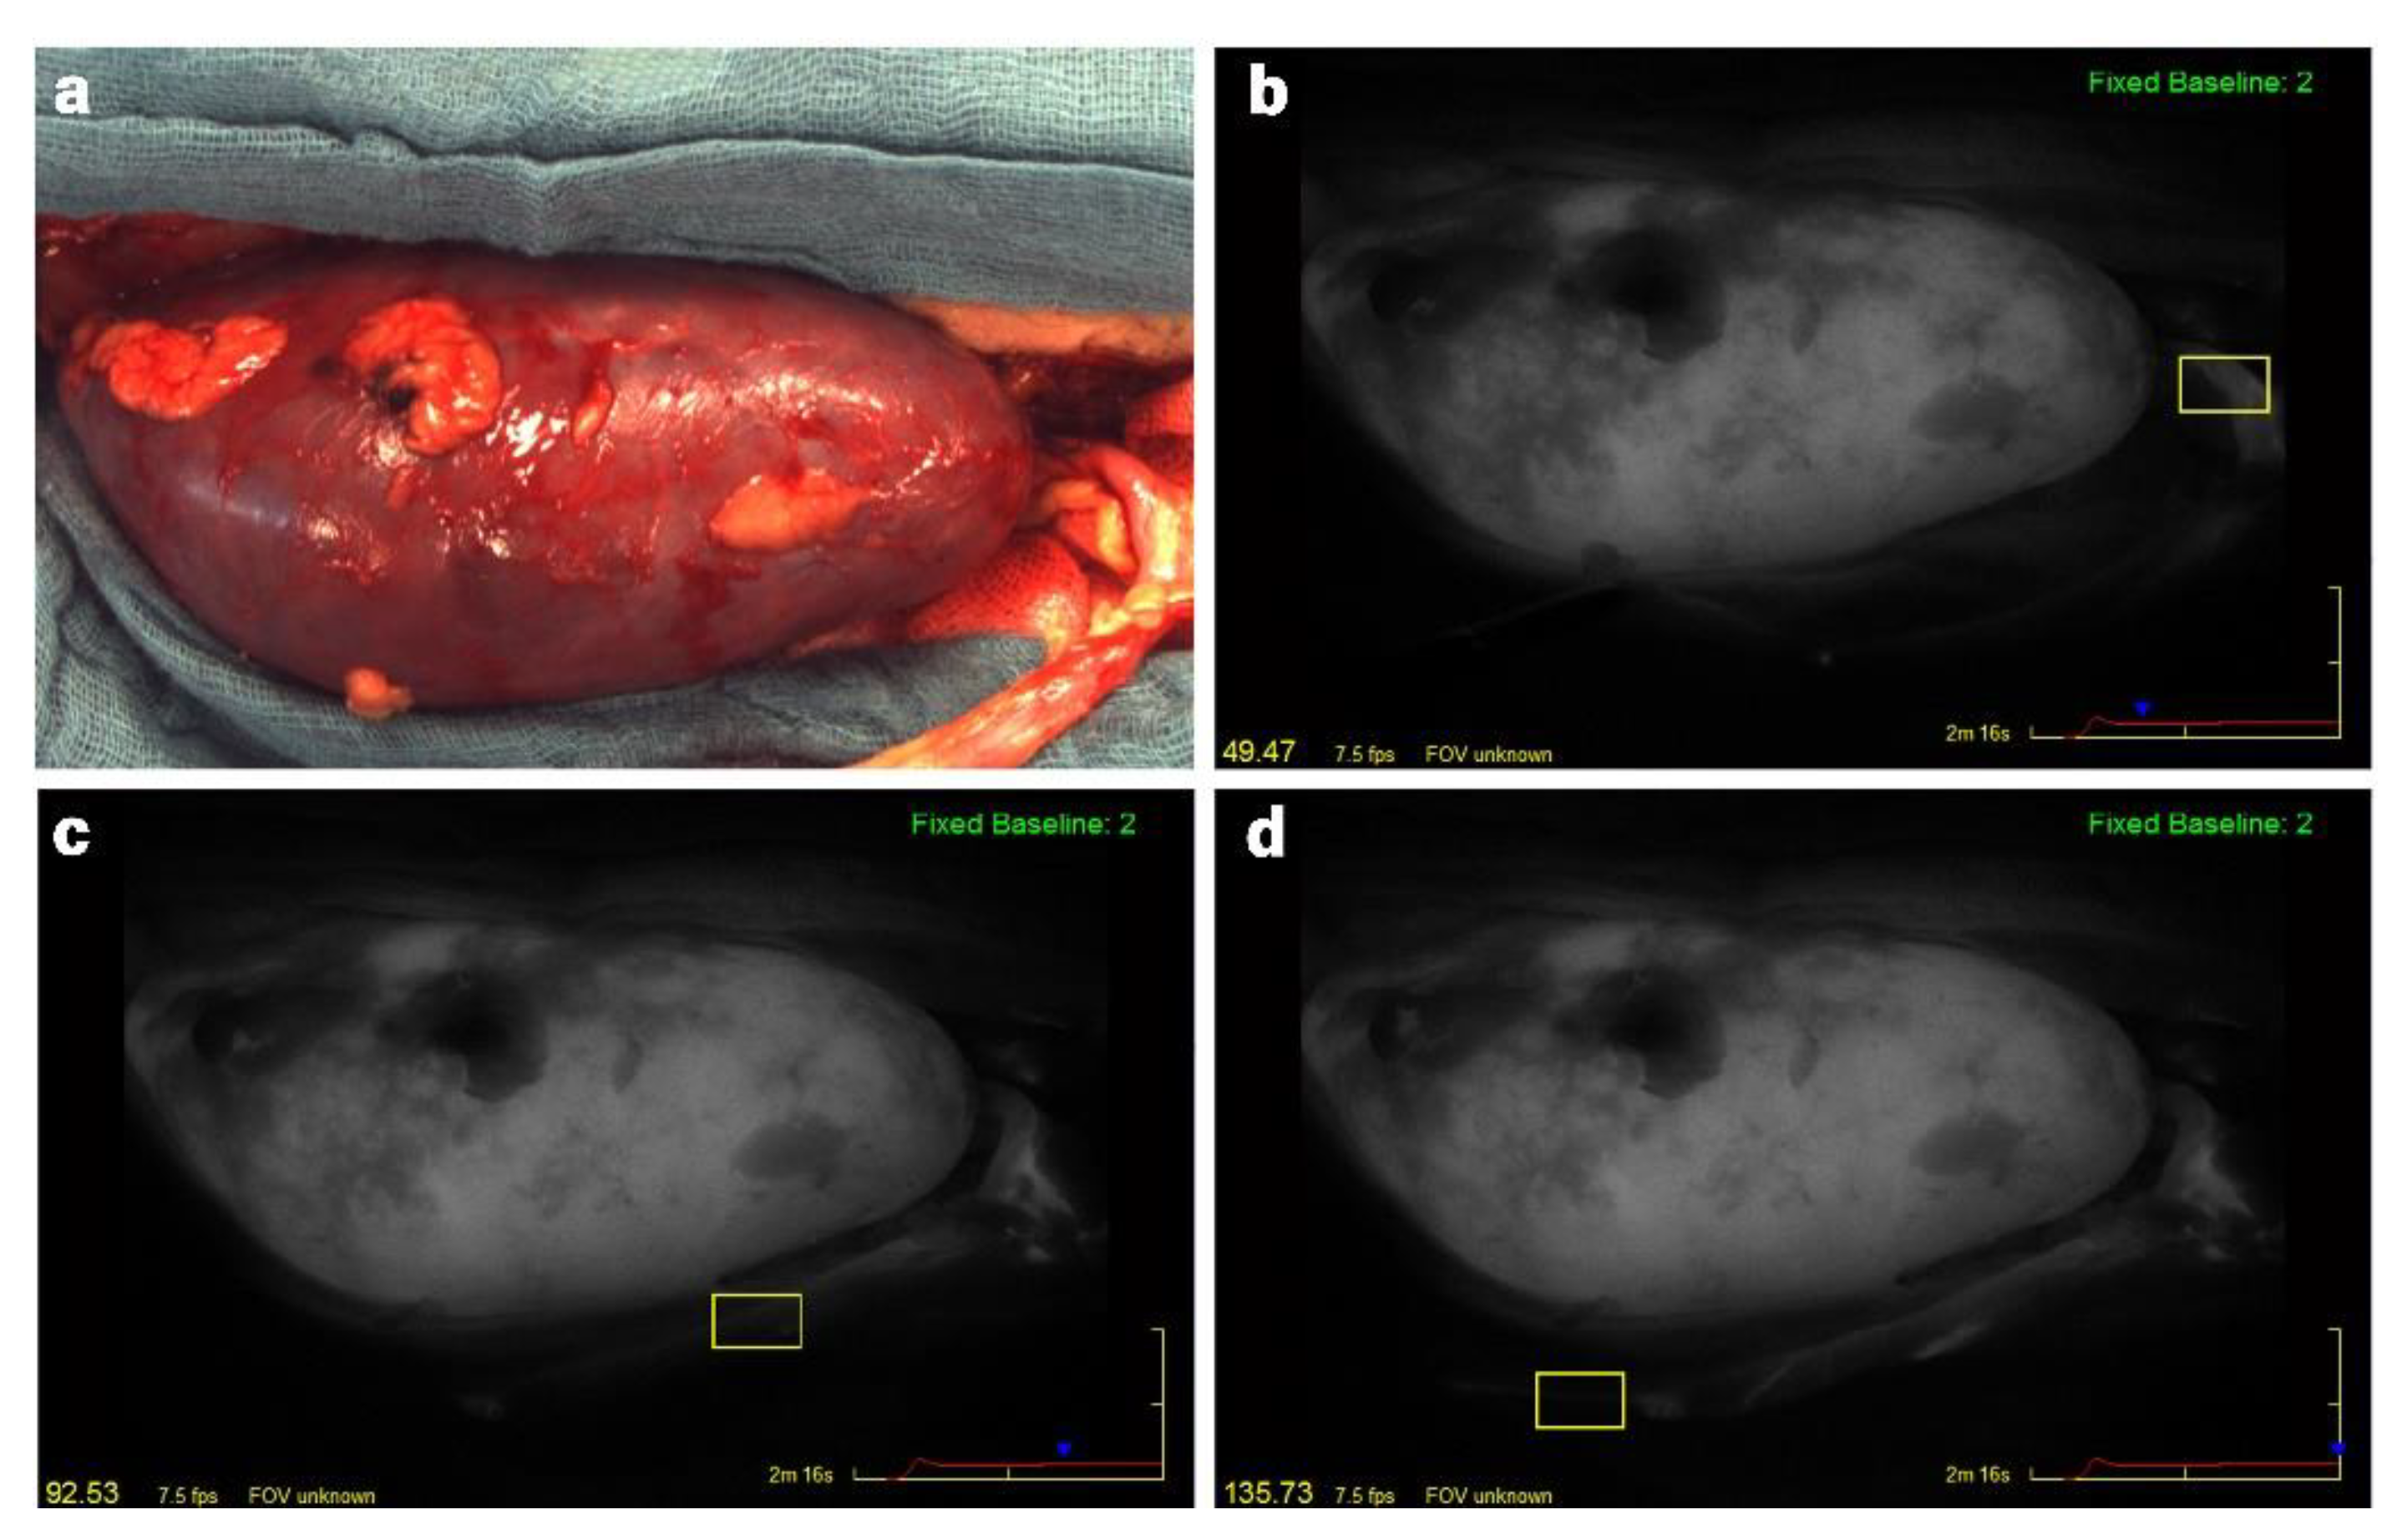

2.2. Surgical Procedure and ICG Fluorescence Angiography

2.3. Analysis of Fluorescence Angiography Video Sequences and the Ureteral Perfusion